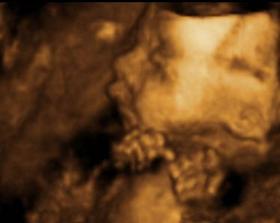

Tešíme sa na nášho drobca